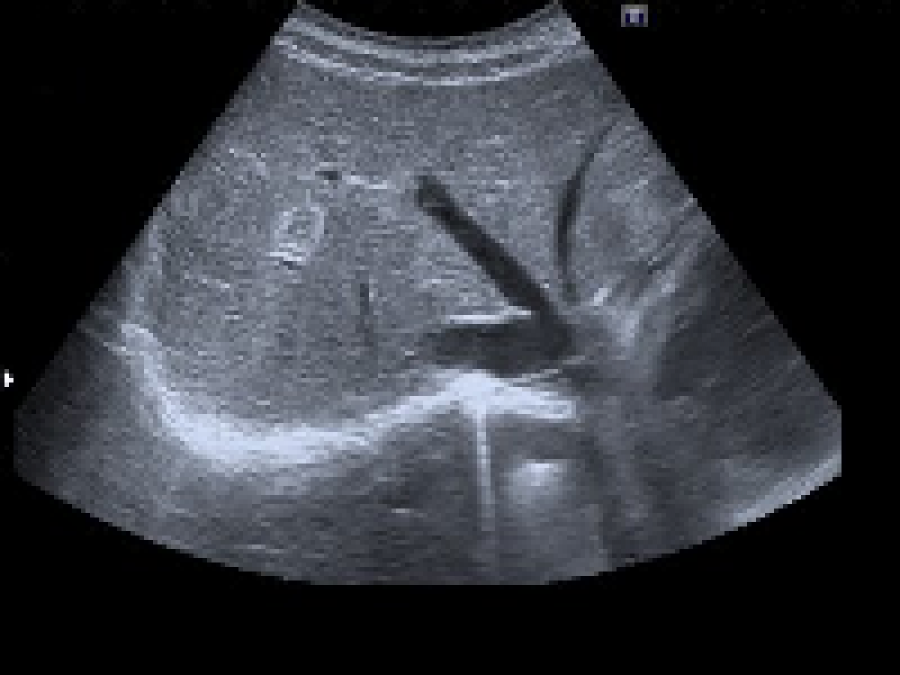

L’échographie utilise des ultra-sons. Ils sont produits par une sonde placée sur la peau du patient ; ils passent à travers la peau grâce à un gel de contact et sont réfléchis partiellement par les organes qu’ils traversent.

Les ultra-sons réfléchis sont enregistrés par la sonde et permettent de créer l’image en coupe visible sur l’écran.

Le doppler peut être associé à l’échographie. Au cours du doppler, les flux des vaisseaux sont codés en couleur selon leur direction et leur vitesse, la mesure des vitesses et des résistances vasculaires est effectuée.